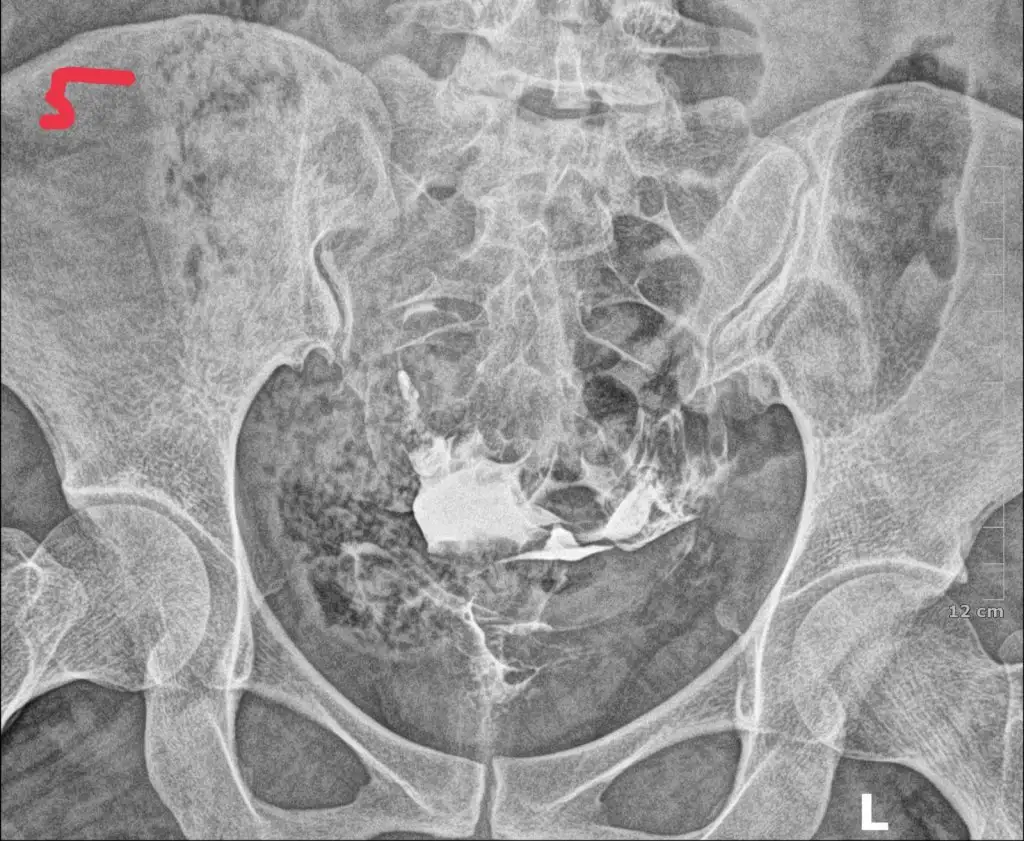

tüp bebek merkezine yönlendirdi . Orada daha detaylı kan tahlili muayene yapıldı adet bitimi hsg çekindim . Çekindiğim gün işlem başında doktor iki tüpün de tıkalı canım dedi ben ağlamaya başladım ağlama sakinleş ilaç ile açmaya çalışacağım eğer olmazsa ameliyat olursun demişti . İşleme 4-5 kez tekrarladık . Sonra iyi kötü bi gidiş oldu . O zaman ki ilgilenen doktora olanları anlattım böyle birşey imkansız tüpler açık o ara kasmışsındır dedi ama hiç kasmadım inanın ki . 6 ay dene olmazsa gel dedi 6 ay sonra gittim o doktor yoktu . Başka doktora geçtim oda sızıntının yeterli olmadığını hala tıkalı olduğunu ve içeriye iyi bir müdahale yapılması gerektiğini söyledi . Ameliyat önerdi . Laparoskopi olacağım ayın 27 sinde . Sonrasında aşılama yapmaya başlıcaz olmazsa